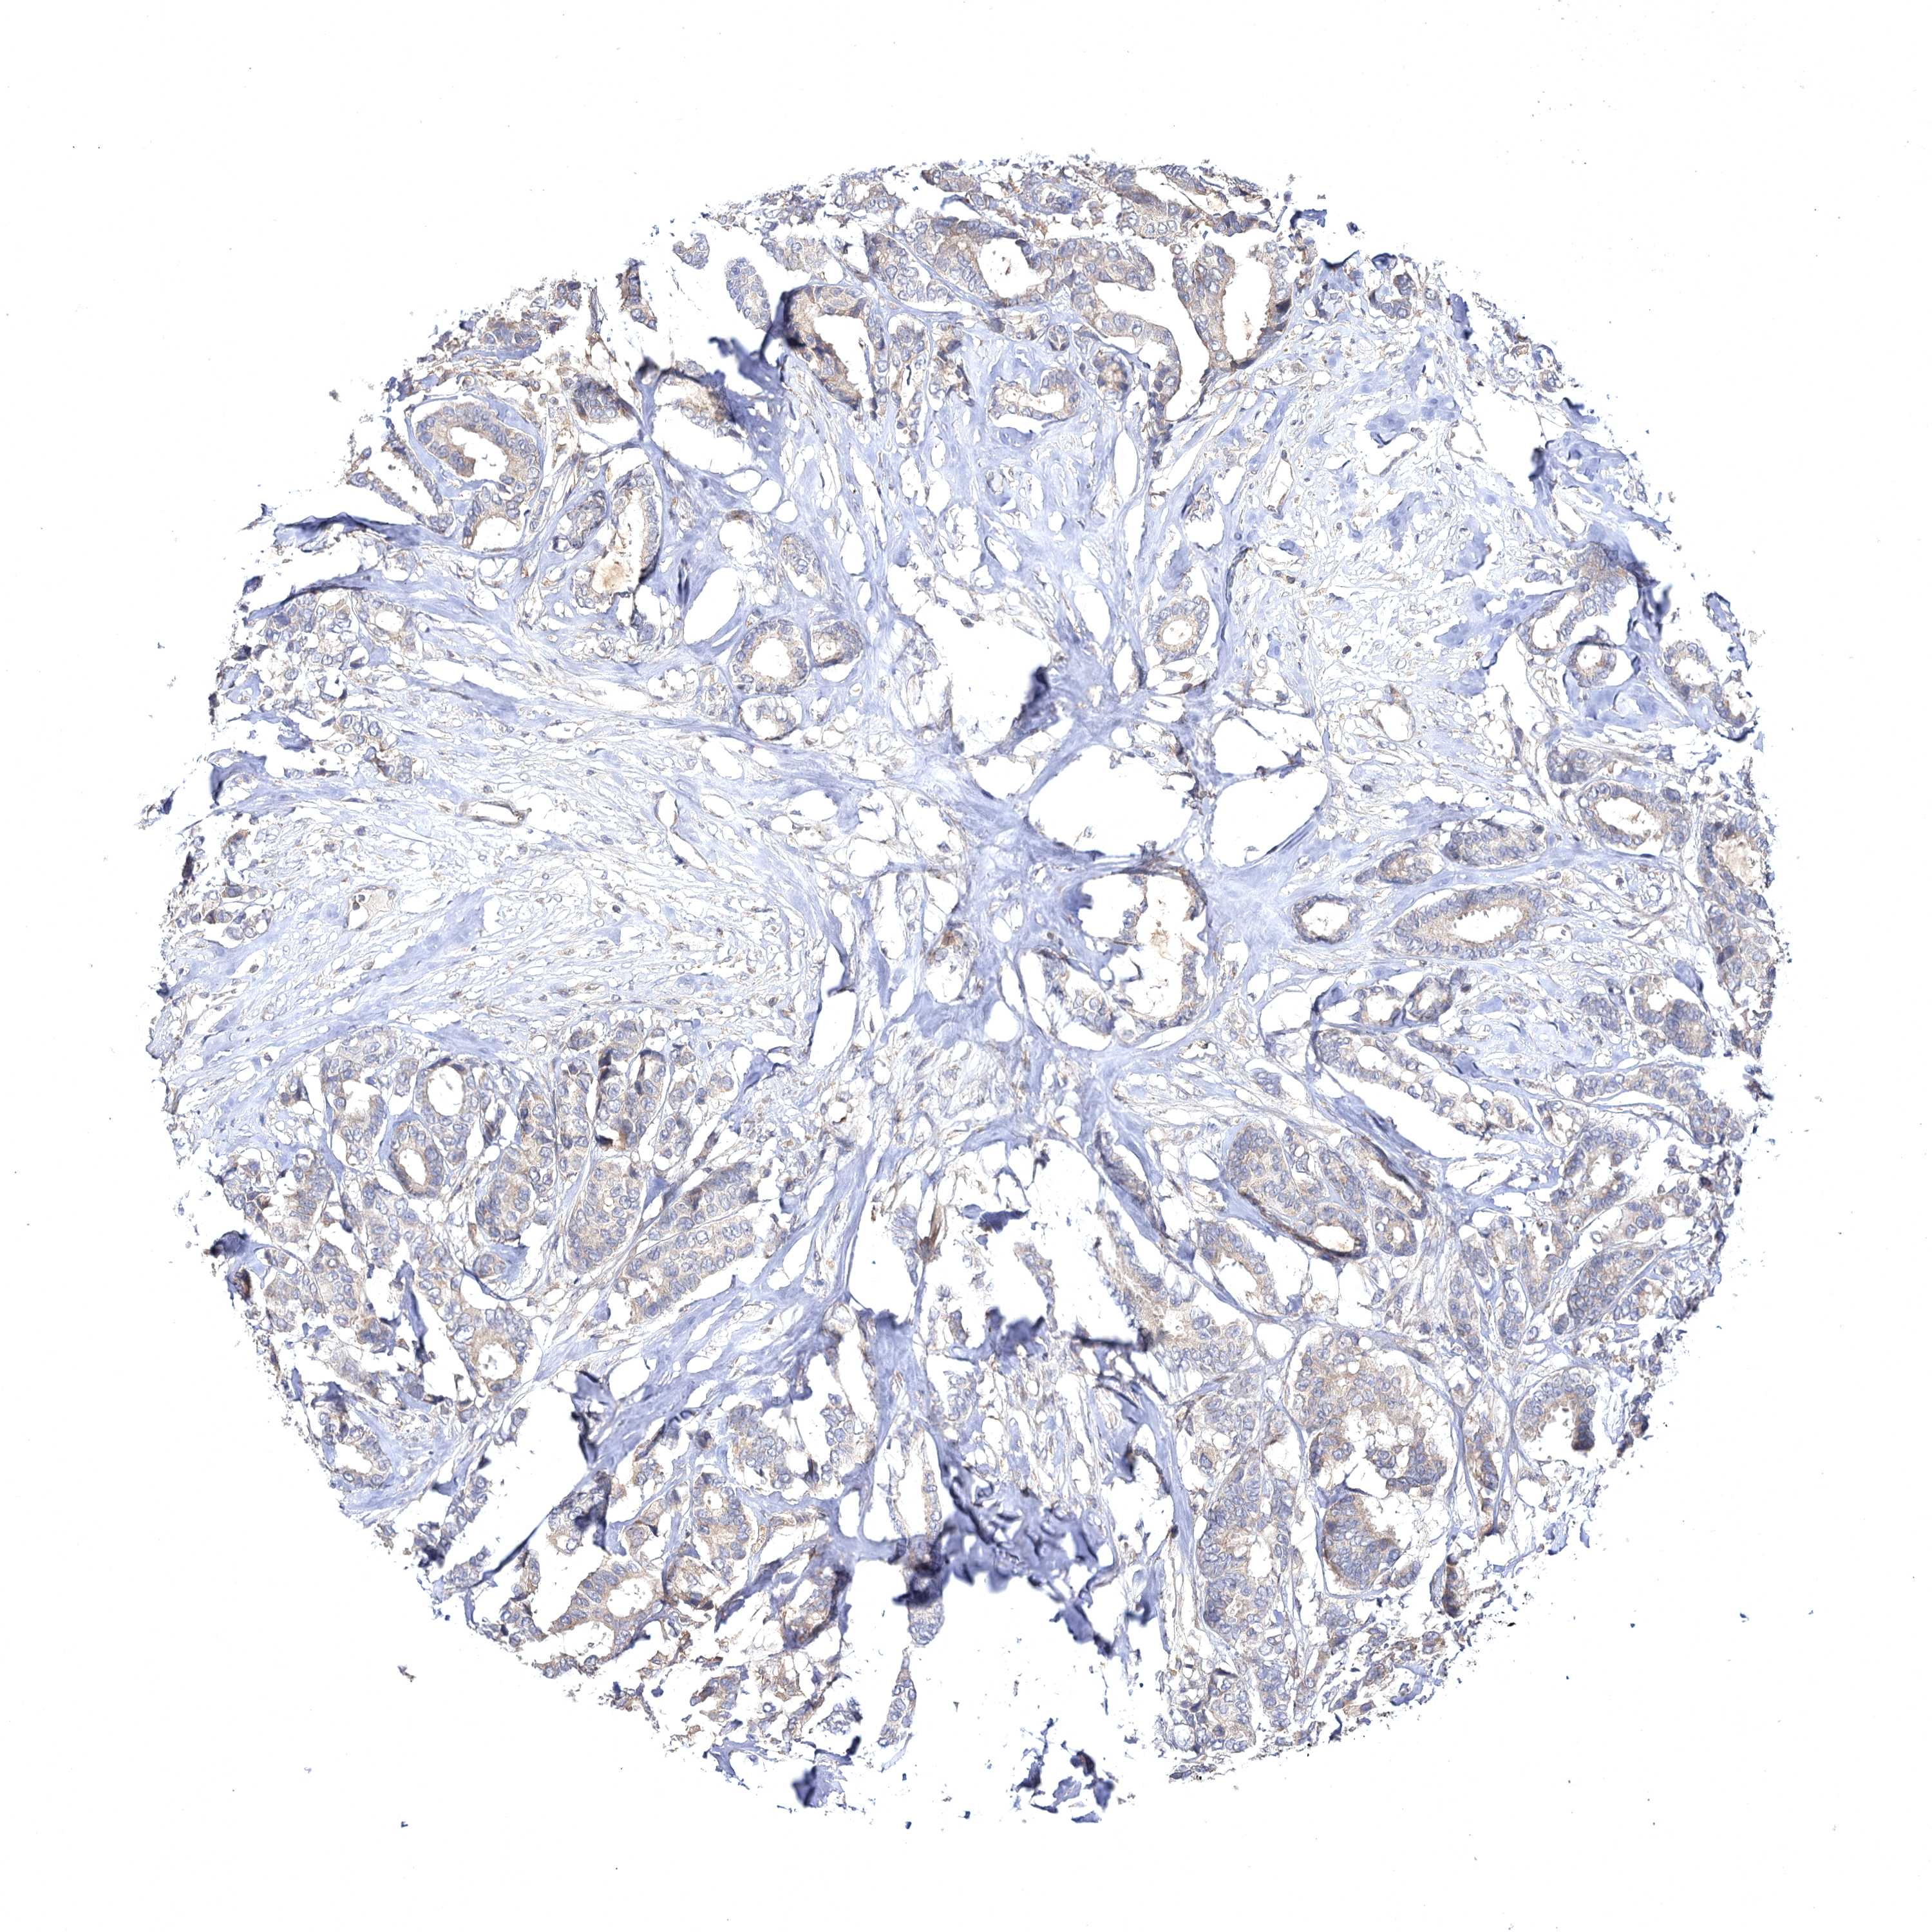

CANCER BREAST CANCER Show tissue menu

Breast cancer

Human cancer